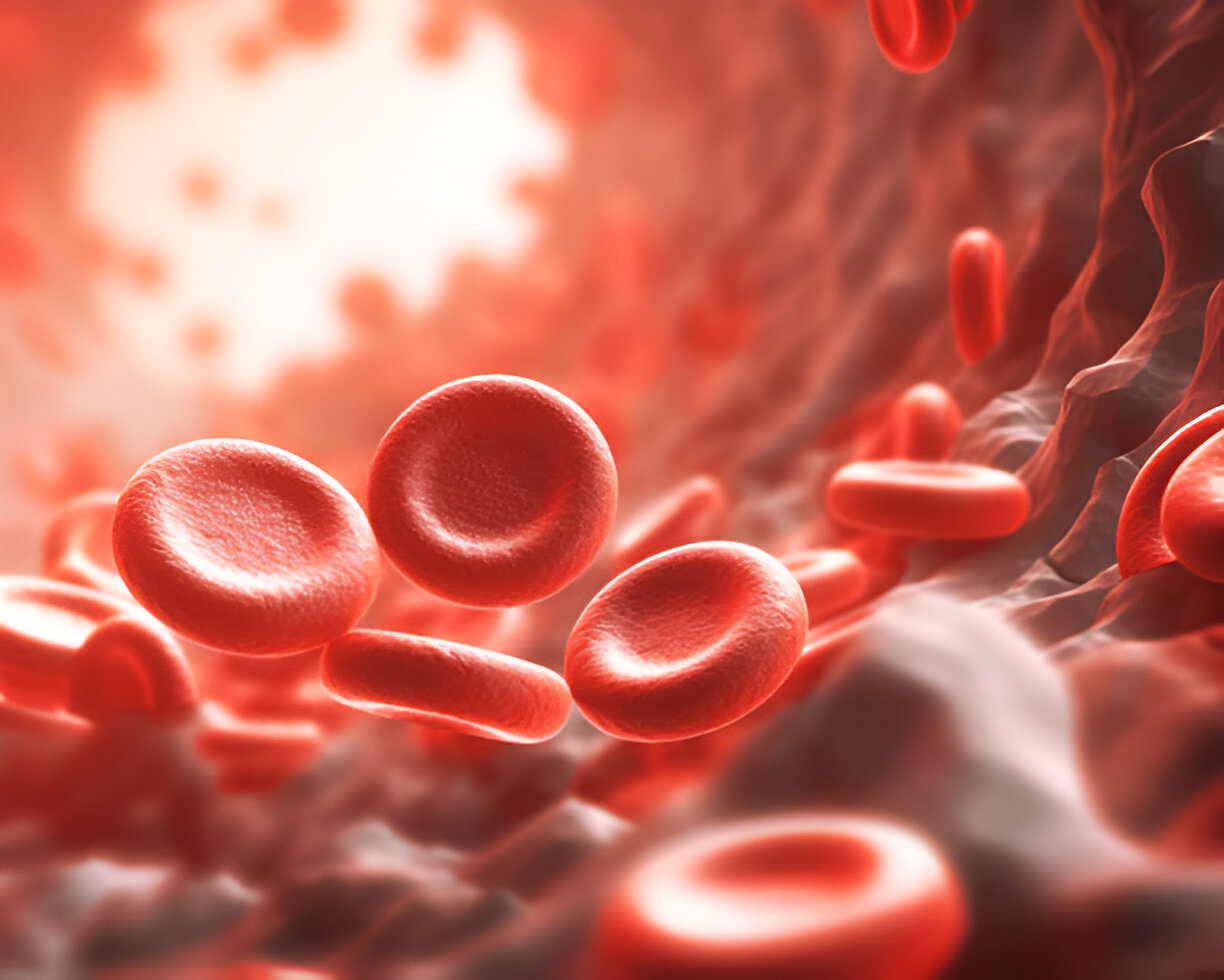

Kraujas – tai gyvybiškai svarbi mūsų organizmo dalis: jis nuolat juda kraujagyslėmis, perneša įvairias medžiagas ir užtikrina normalų visų organų...

Skaityti daugiauDetailsB limfocitai: rūšys ir funkcija

B limfocitai – itin svarbios mūsų organizmo apsaugos imuninės sistemos dalys. Šie balti kraujo kūneliai sukuria specifinius baltymus – antikūnus,...

Skaityti daugiauDetailsRaudonųjų kraujo kūnelių – eritrocitų funkcija

Raudonieji kraujo kūneliai perneša deguonį iš plaučių į kūno audinius. Audiniai naudoja deguonį energijos gamybai ir išskiria anglies dioksidą kaip...